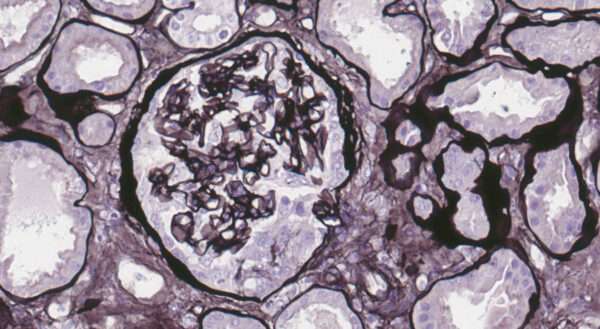

La biopsia renal es un paso esencial en el diagnóstico de la glomerulonefritis anti-GBM, ya que proporciona evidencia directa del daño glomerular. En la mayoría de los casos, el análisis de la biopsia renal muestra la formación de semilunas en los glomérulos, un hallazgo característico de la glomerulonefritis rápidamente progresiva. Las semilunas se forman debido a la proliferación de células en la cápsula de Bowman, una respuesta a la lesión glomerular severa que ocurre como resultado de la actividad inflamatoria mediada por los anticuerpos anti-GBM. La semiluna es una estructura patológica que se observa típicamente en las glomerulonefritis que cursan con rápida pérdida de función renal.

El estudio inmunofluorescente es crucial para confirmar el diagnóstico. En la glomerulonefritis anti-GBM, el análisis por inmunofluorescencia muestra una tinción lineal de inmunoglobulina G (IgG) a lo largo de la membrana basal glomerular. Esta tinción lineal es altamente característica y se debe a la unión de los anticuerpos anti-GBM a los epítopos específicos del colágeno tipo IV en la membrana basal. Este patrón de tinción es distinto de otras enfermedades glomerulares autoinmunitarias, como las glomerulonefritis asociadas con complejos inmunes, que suelen mostrar patrones más granulados o en «flecos» de tinción. La identificación de esta tinción lineal de IgG en la biopsia renal es un hallazgo diagnóstico fundamental que permite confirmar la presencia de anticuerpos anti-GBM y establecer el diagnóstico de glomerulonefritis anti-GBM.